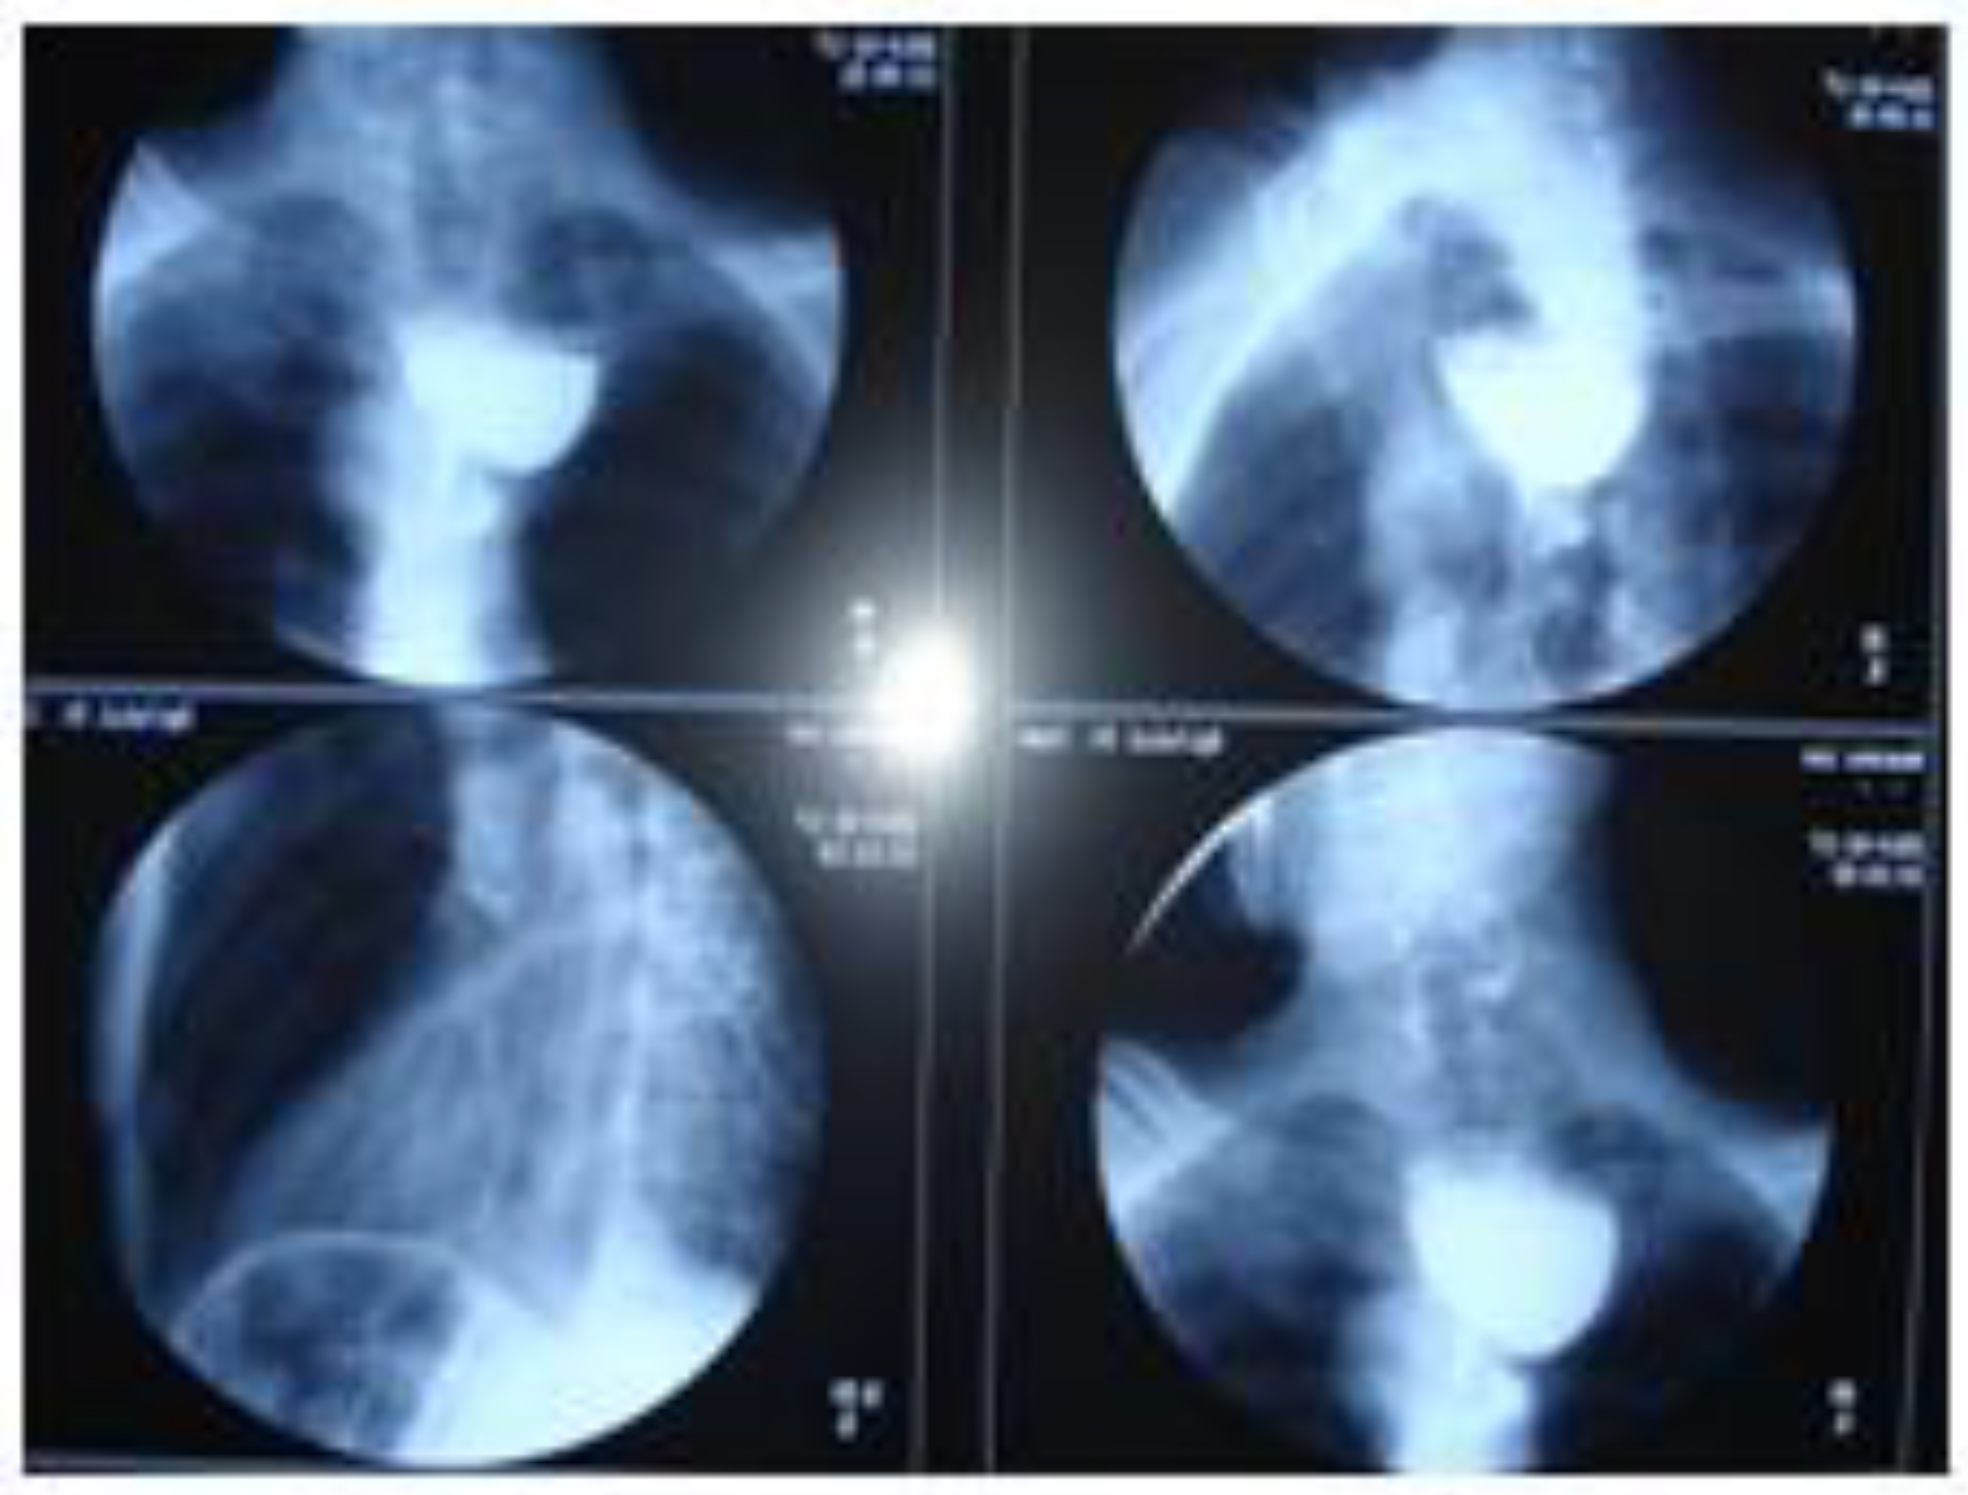

Zenker’s Diverticulum and Squamous Esophageal Cancer: A Case Report

Case Report